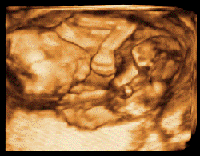

• Add-on 3D/4D Ultrasound Imaging System which acquires 3D volume image by being added to existing 2D ultrasound systems.

• Simple Operation, Fast working, Supreme Image.

• Cost effective and easy upgrade 2D ultrasound into 3D.